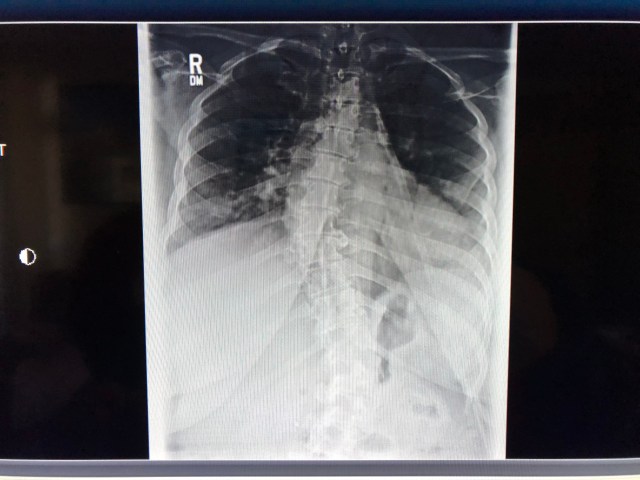

The most problematic issue has been my spine. I have scoliosis and it has gotten markedly worse over the past few years while working as a professional driver.

Here are some recent x-rays of my back: